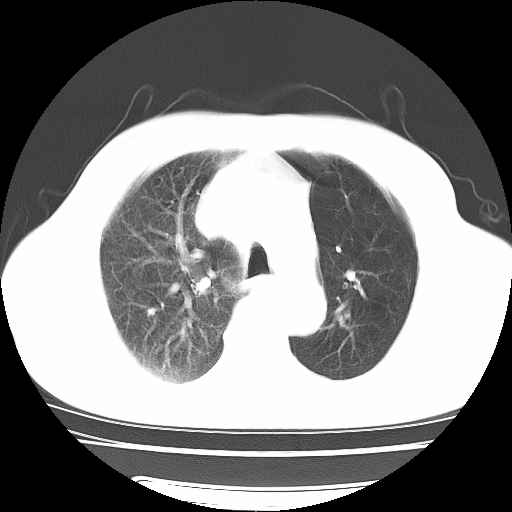

男,71岁,咳嗽,气喘10年,再发并咯血.胸片见气胸

考虑  左肺中心型肺癌伴阻塞性肺炎,肺不张,纵膈淋巴结肿大。慢支炎,肺气肿,左侧气胸肺压缩5%

左侧中央型肺癌伴纵膈淋巴结转移。

左肺中心型肺癌伴阻塞性肺炎,肺不张,纵膈淋巴结肿大

1)考虑左肺中心型肺癌伴阻塞性肺炎、左肺下叶肺不张、左侧肺气肿,纵膈淋巴结转移。2)左侧气胸(肺组织压缩约5%)。

左肺中心型肺癌伴阻塞性肺不张、肺气肿 。

1)考虑左肺中心型肺癌伴阻塞性肺炎、左肺下叶肺不张、左侧肺气肿,纵膈淋巴结转移。2)左侧气胸。